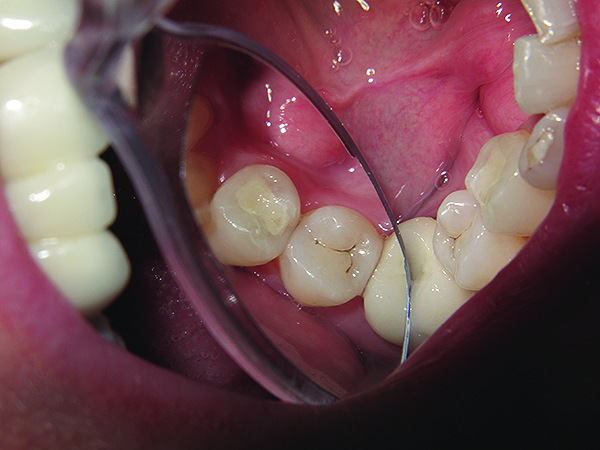

Yet, most of the patients do not have “ideal” mouths. They present in conditions that are often significantly less than that. They present with disease (Figure 4 and Figure 5). It is the author’s opinion that it is a dentist’s professional responsibility to help move patients from a state of constant disease potential to a state of health. This requires much more than telling patients that they must brush and floss more or better. The physical removal of the bacteria-laden plaque is of course important, but most patients are not fully “trained” on how to really do this well. Perhaps this is because it is assumed that they intrinsically know how. But the reality is that most patients do not fully understand how to remove this biofilm. They often rely on over-the-counter chemical agents and quick fixes that they find on the shelves of their supermarkets and pharmacies that promise to solve their dental issues but are often only superficial remedies.

Fig. 4 and Fig. 5 Microorganisms contribute to the localized chemical dissolution of the dental structure.

Figure 5